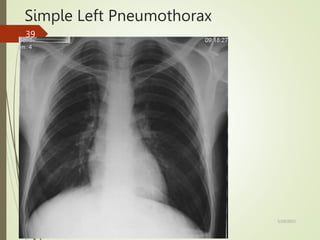

Simple Left Pneumothorax

No mediastinal shift

Small pleural

effusion

(common

finding)

Visceral

pleural line

(zoomed

view on next

slide)

5/29/2023